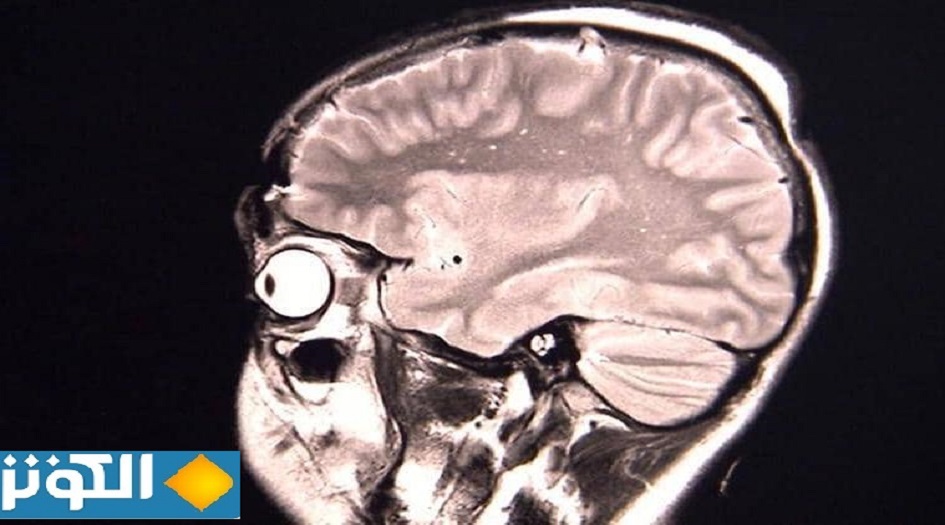

ورغم أن ثلاث حالات ليست كافية للوصول إلى استنتاجات على نطاق واسع بشأن الوباء، إلا أن العلماء يعتقدون أن الأعراض ربما تكون نتيجة للاستجابة المناعية التي تسبب التهابا في أجزاء معينة في الدماغ.